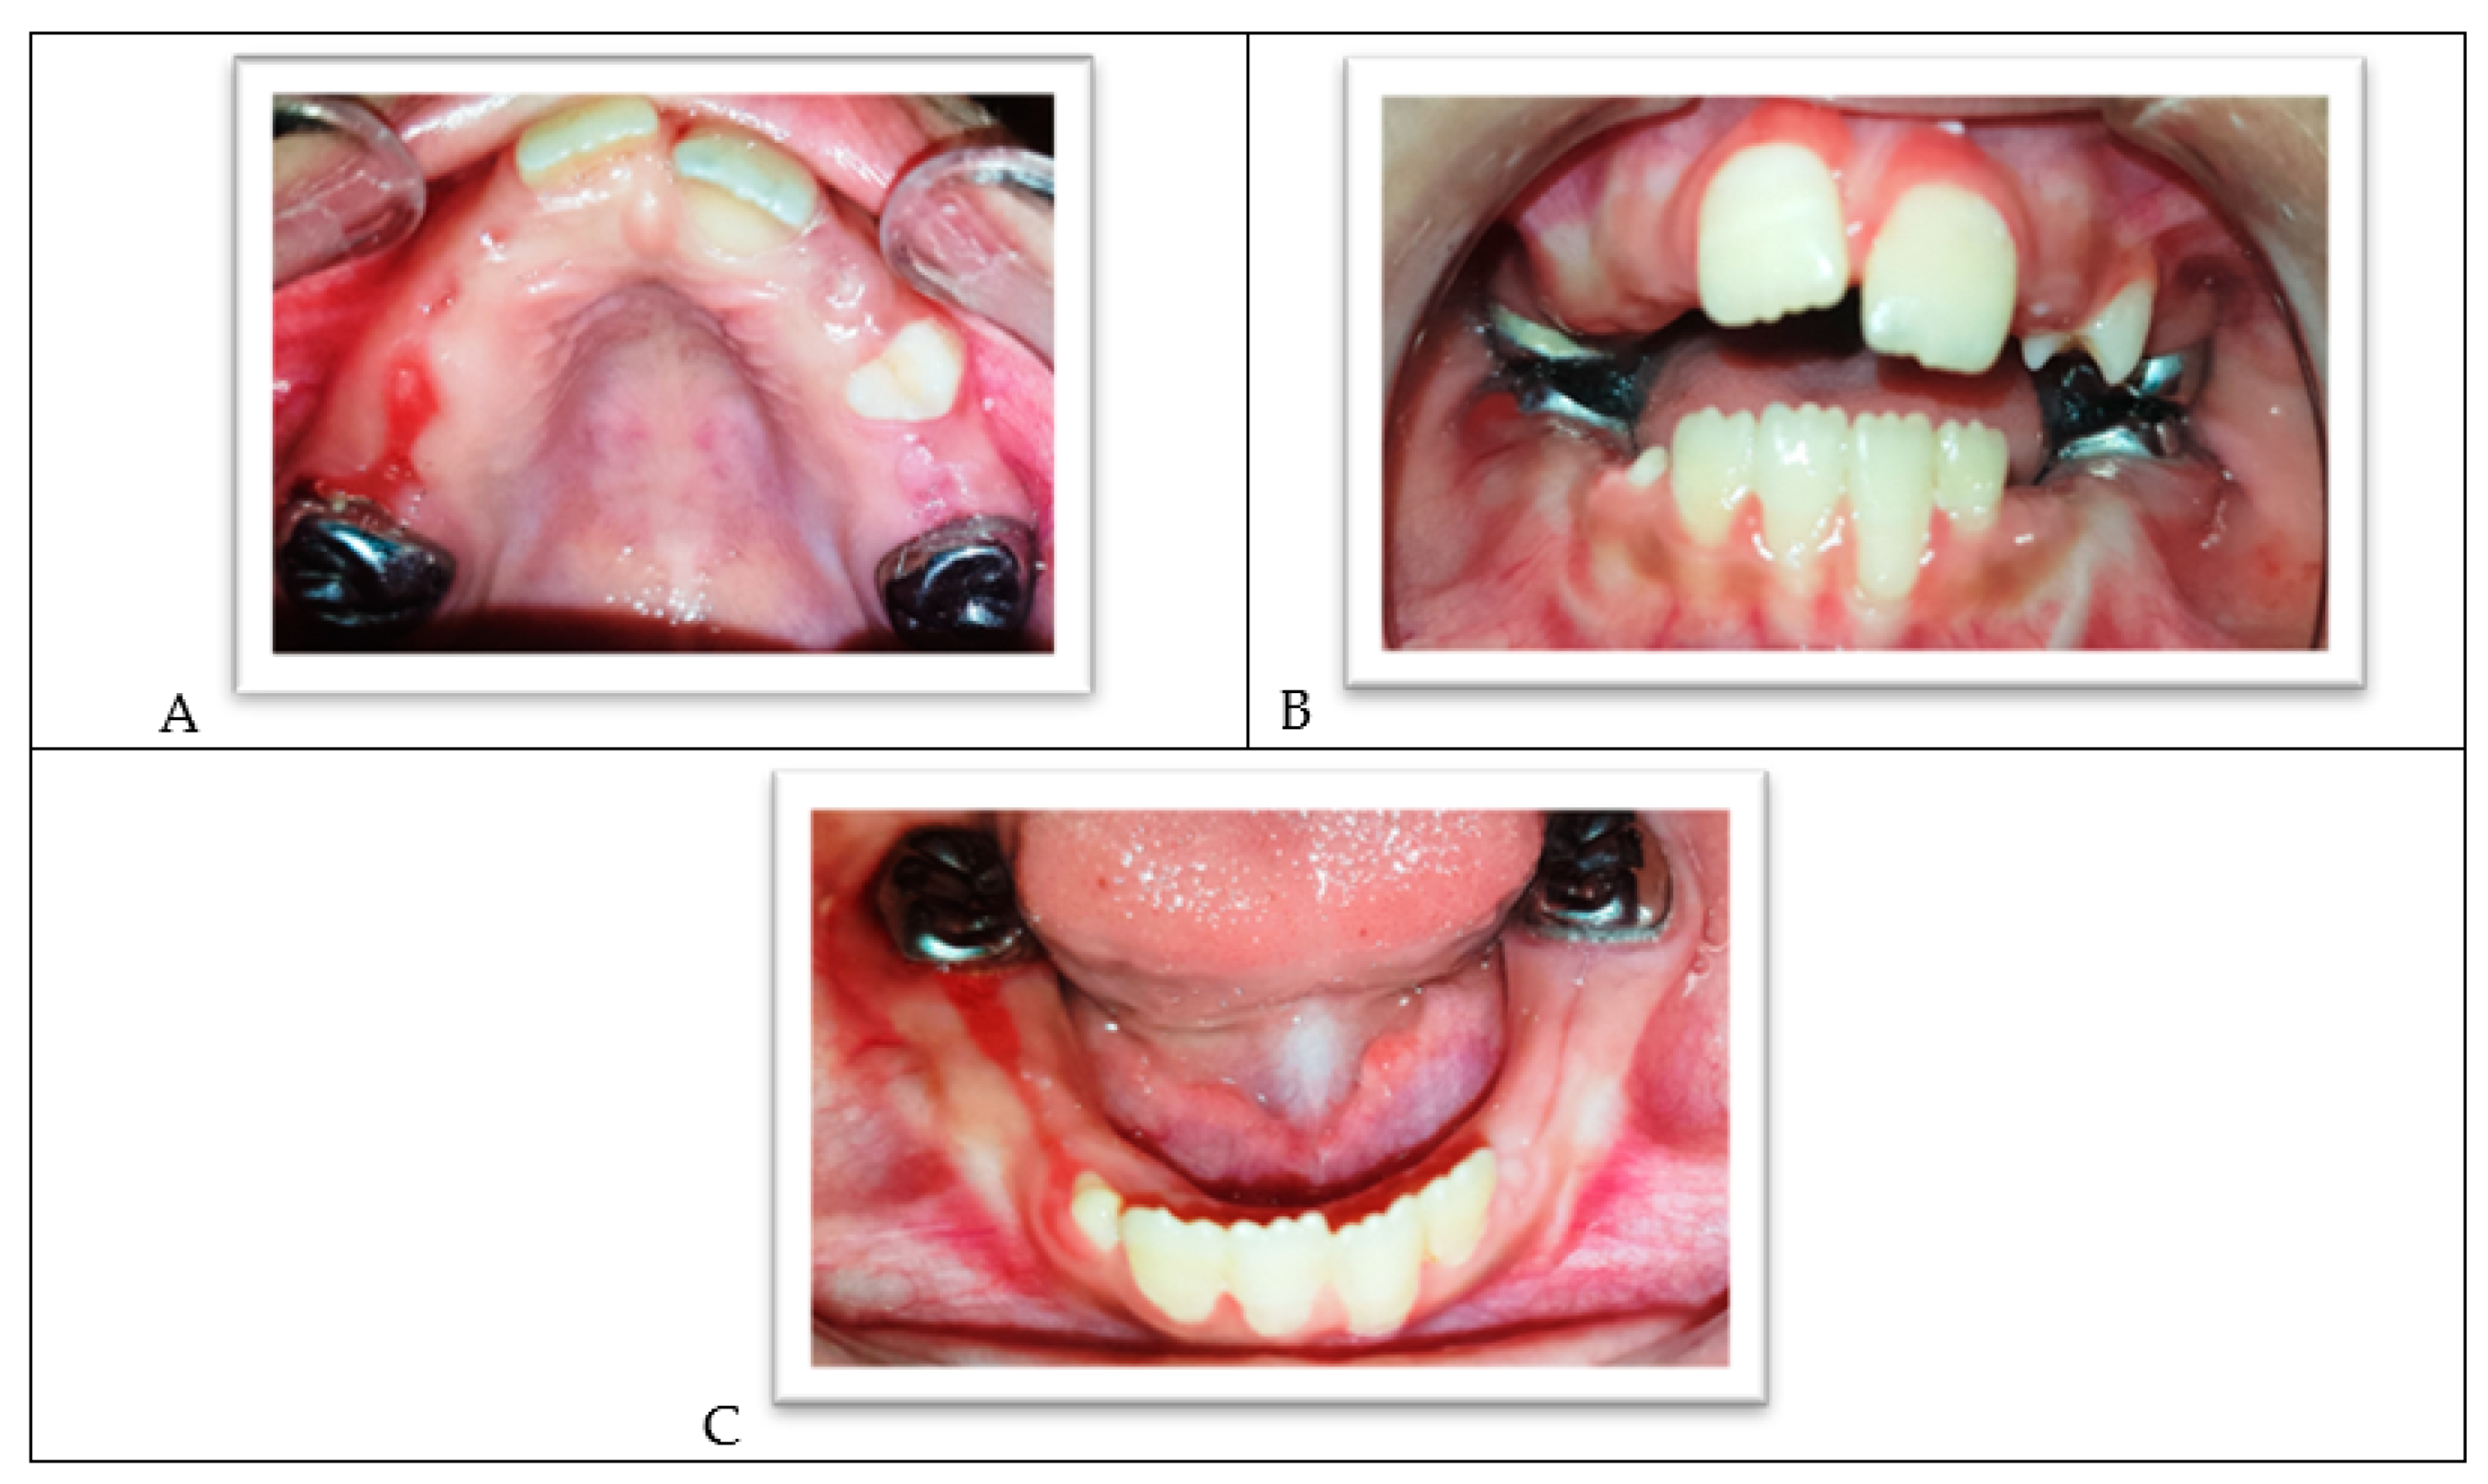

2. Case Report

Clinical and Radiographic Follow-Up